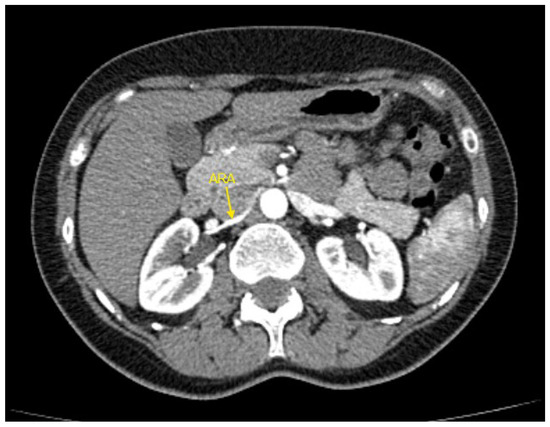

Figure 2. Contrast-enhanced CT imaging of a 47-year-old female patient with refractory hypertension revealed an accessory renal artery in the left kidney, shown by the yellow arrow. ARA—accessory renal artery; CT—computed tomography.